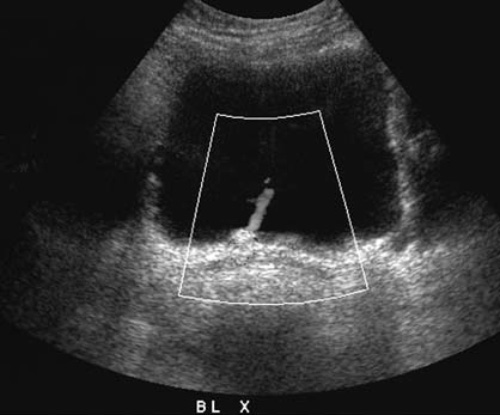

Артефакт ложного потока по сути является потоком реально жидкости, но не крови, например, амниотическая или асцитическая жидкость. В качестве примера ложного потока также можно привести струю в мочевом пузыре. Таким образом, используемый в повседневной практике термин «ложный поток» по сути является неправильным, поскольку более корректно применять термин «некровянной поток» (фото 3, 4, 5).

Фото 3. УЗИ мочевого пузыря: струя мочи в мочевом пузыре. Поперечная проекция основания мочевого пузыря демонстрирует нормальный выброс жидкости из правого мочеточника